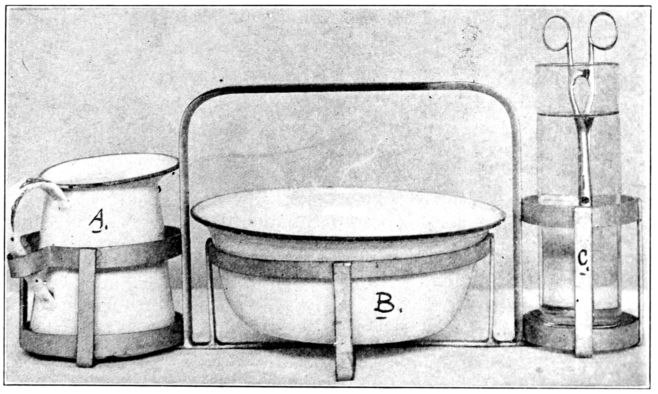

| 118. | Equipment in rack used in Fig. 117 | 337 |

| 146. | Breast tray recommended to expectant mothers by Maternity Centre Association | 417 |

| xxiii147. | Baby’s toilet tray recommended to expectant mothers by Maternity Centre Association | 417 |